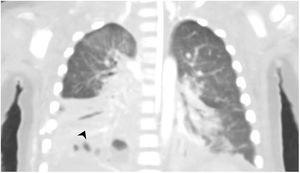

Clinical caseA boy aged 13 months with an unremarkable history was admitted due to toxic shock refractory to amines and respiratory distress syndrome secondary to necrotising pneumonia with empyema (Fig. 1) caused by S. pyogenes. The findings of the evaluation were suggestive of multiple organ failure, with ventricular dysfunction, liver and kidney failure and severe metabolic acidosis with hyperlactataemia, with the patient requiring venoarterial extracorporeal membrane oxygenation (VA-ECMO) for 10 days.

As the disease advanced, he developed distal ischaemia in the extremities (Fig. 2), with proximal progression and hard necrotic plaques. The CT angiogram evinced necrotising fasciitis in the right upper extremity with patchy myositis and extensive ischaemia in the extremities and trunk requiring escharotomy and debridement, in addition to diffuse enterocolitis with intestinal perforation (Fig. 3). At 23 days of admission, in a multidisciplinary meeting, the decision was made to withdraw life-sustaining treatment due to the need of disarticulation, extensive bowel resection and amputation of all four extremities.